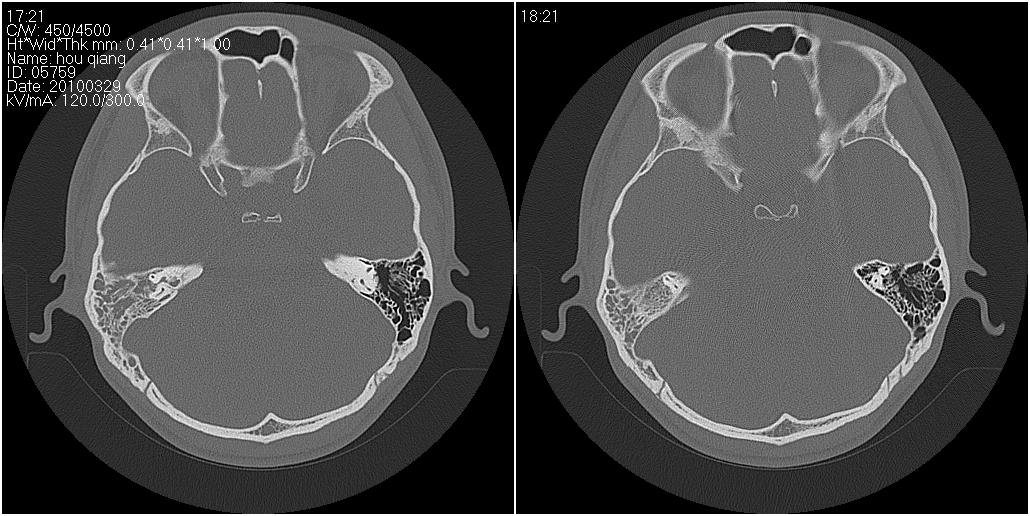

标题: CT25419:男性,18岁。右耳肿、痛5个多月。 [打印本页]

标题: CT25419:男性,18岁。右耳肿、痛5个多月。

右侧中耳乳突炎累及外耳道,鼻咽腺样体肥大。

1)右侧慢性中耳乳突炎并右侧中耳腔及外耳道肉芽肿或胆脂瘤形成。2)鼻咽腺样体肥大。